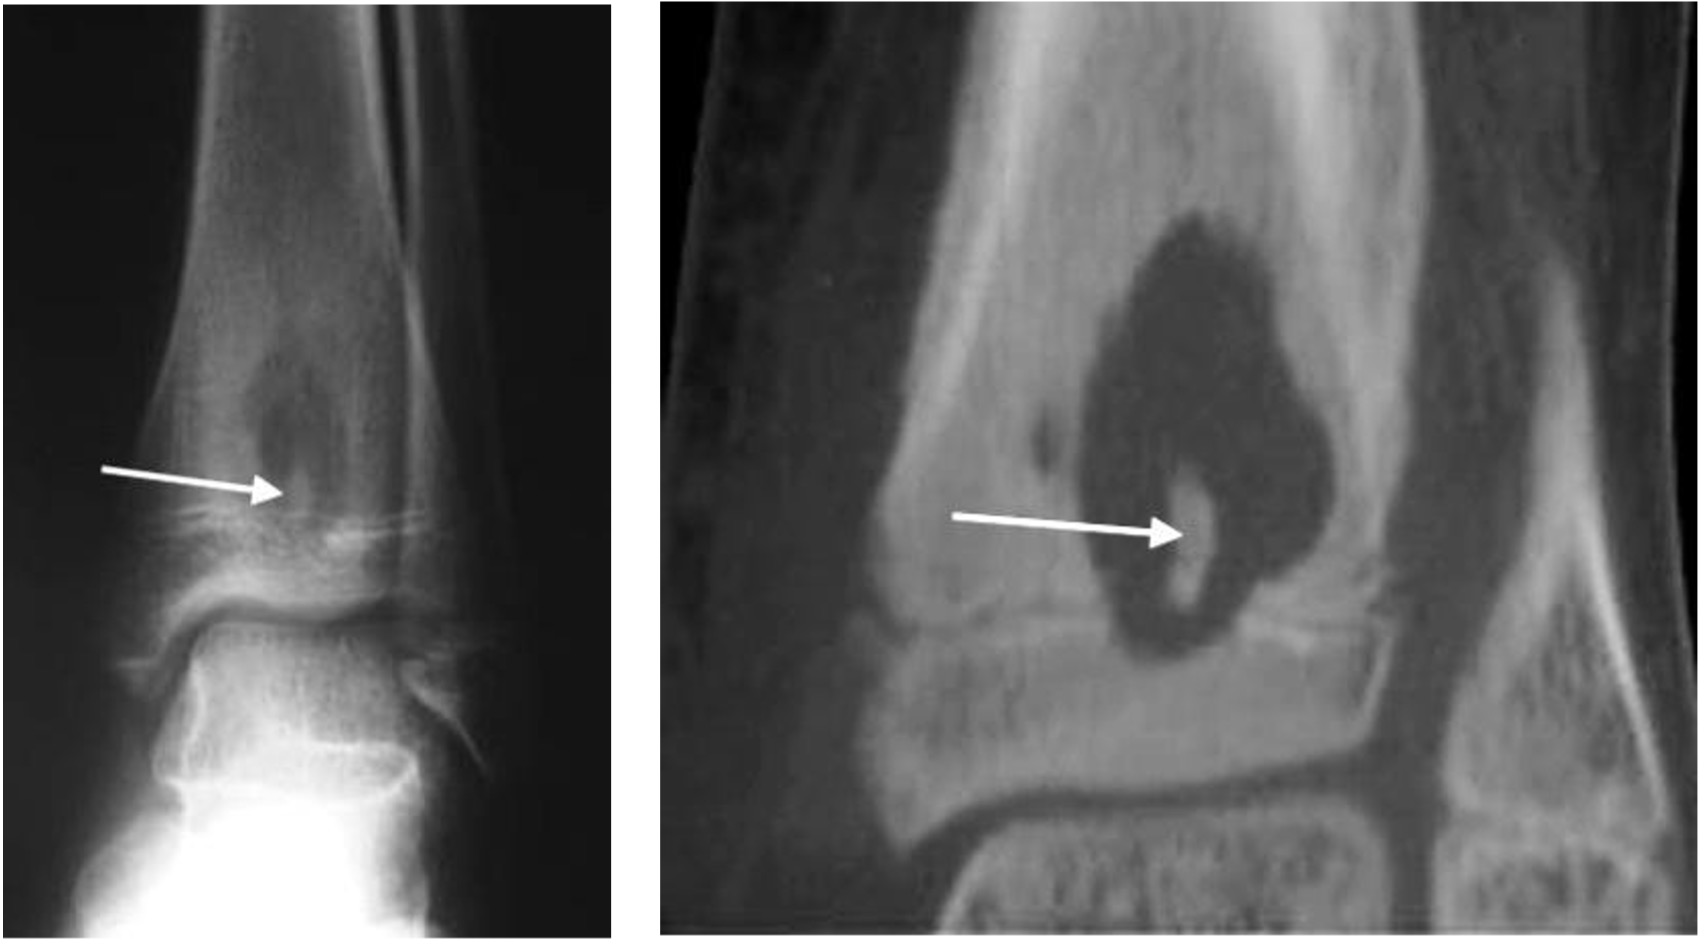

Abscess in distal tibia with sclerotic sequestrum on plain radiograph and CT (arrow)

Osteochondritis dissecans medial talar dome (arrow)